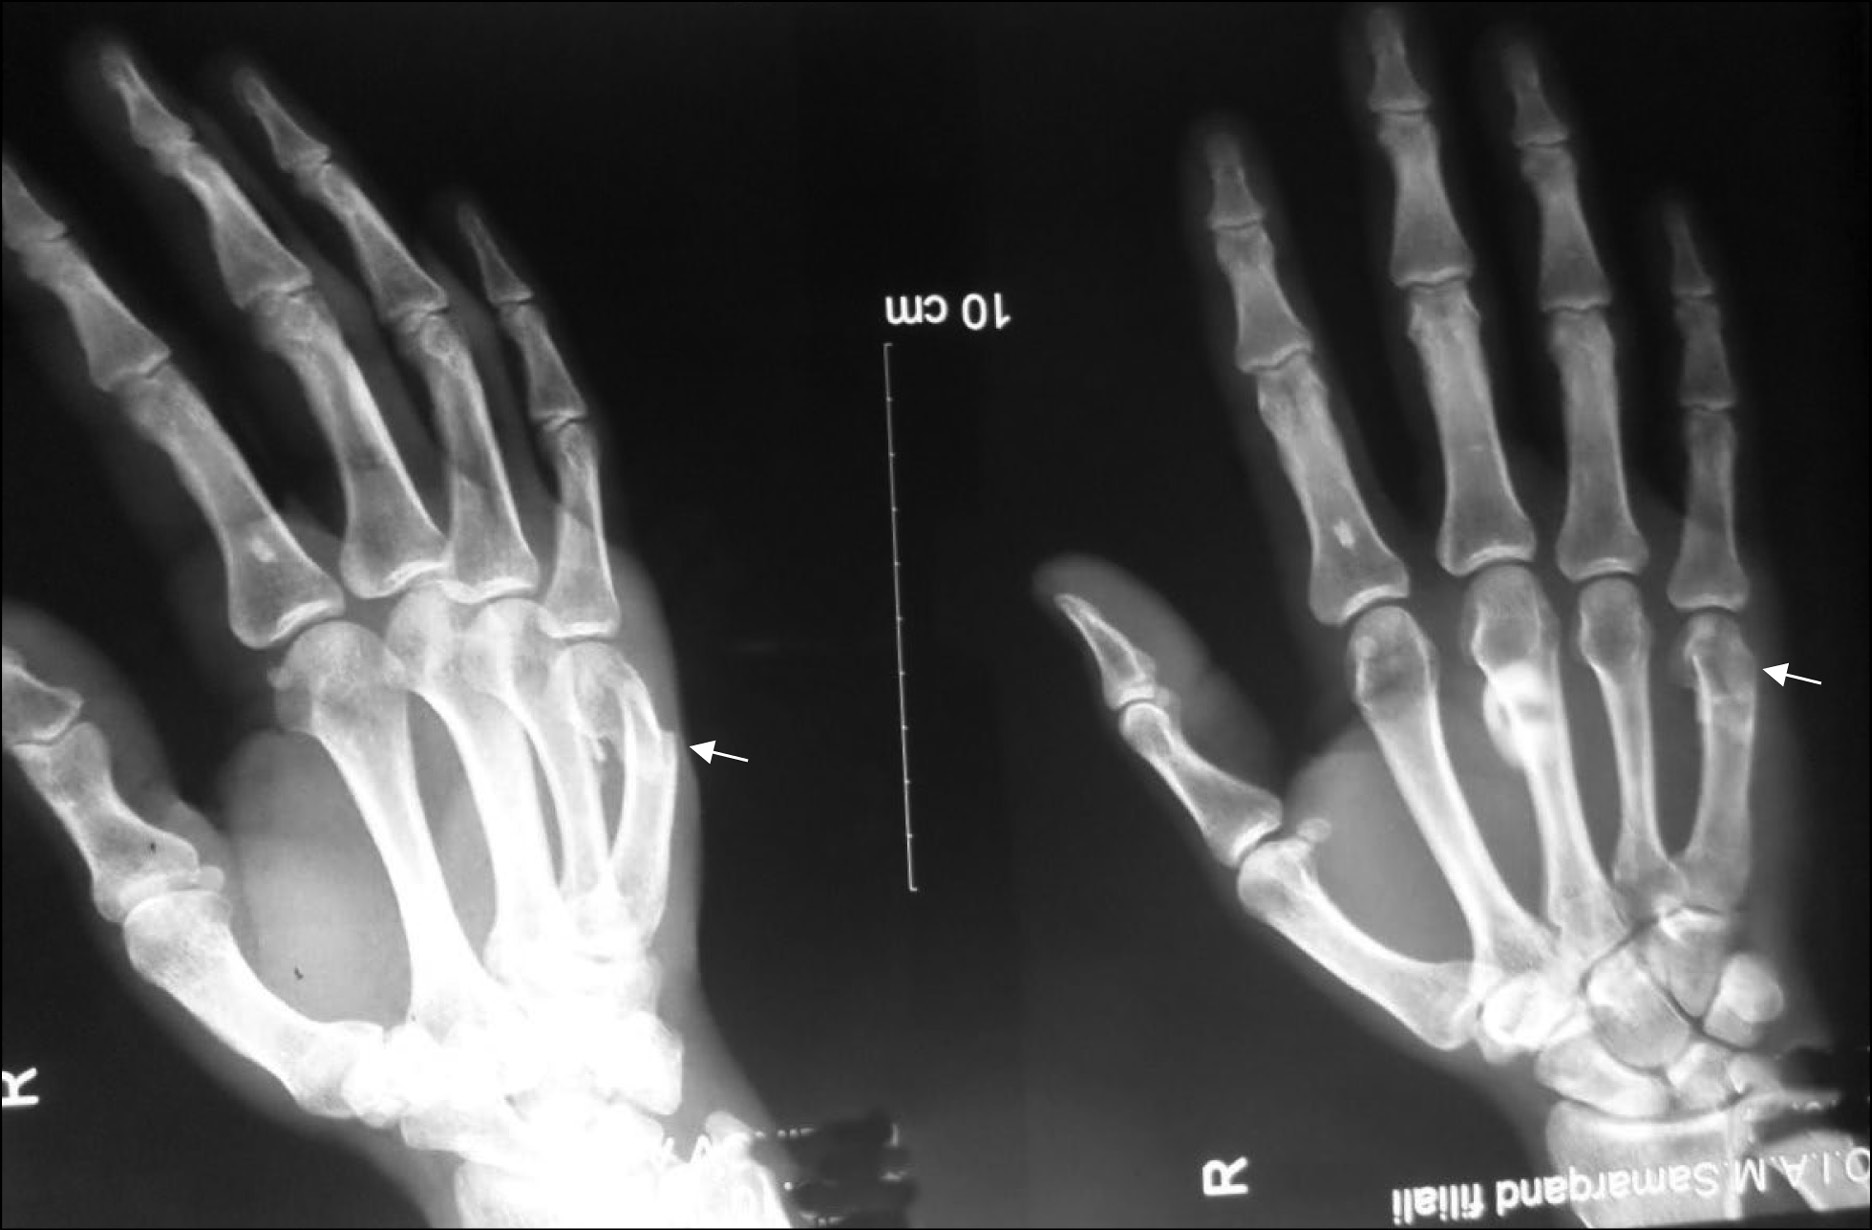

Рис. 1. Рентгенограмма правой кисти, прямая проекция. Пациент М., 28 лет, падение на плоскость, диагноз: «Вертикальный неполный перелом ладьевидной кости правой кисти (тип А2); давность перелома 15 сут» (место перелома указано стрелкой).

Группа 1. Изучены закрытые переломы костей запястья у 24 лиц мужского пола в возрасте от 15 до 48 лет, получивших травмы при различных обстоятельствах: падениях на плоскость (n=11), ударных воздействиях тупыми предметами в область кистей (n=6), велосипедной травме (n=1), столкновениях с движущимся автотранспортом и спортивных играх (n=6). Из табл. 1 видно, что для структуры запястья наиболее характерны переломы ладьевидной (81,8%) кости (рис. 1); переломы остальных костей отмечены в 18,2% случаев.